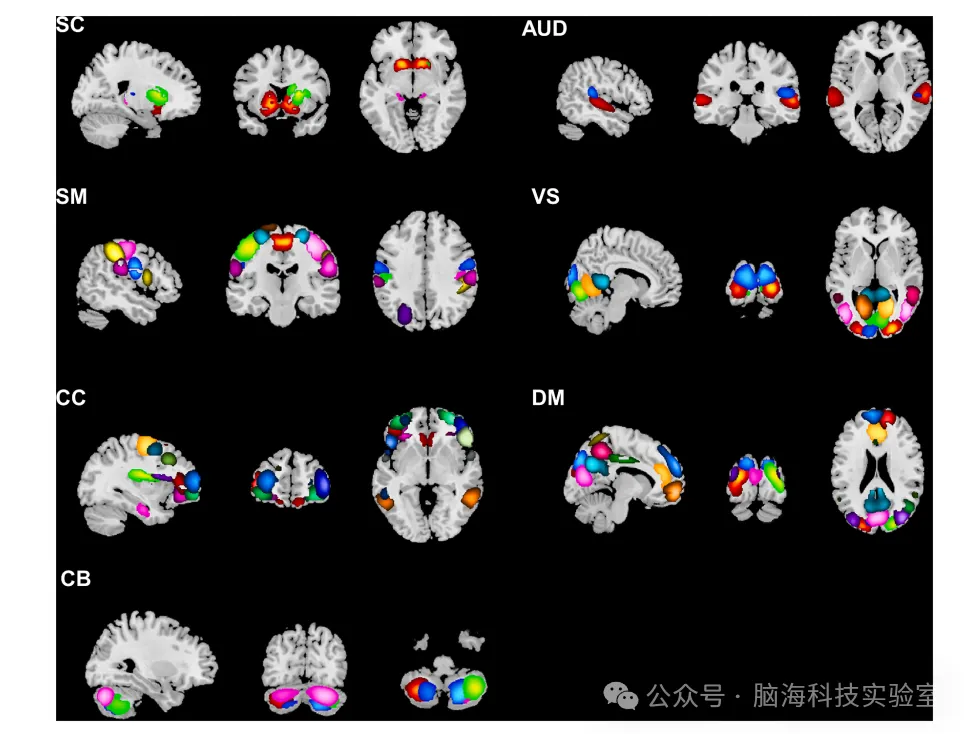

多模态脑影像数据分析平台